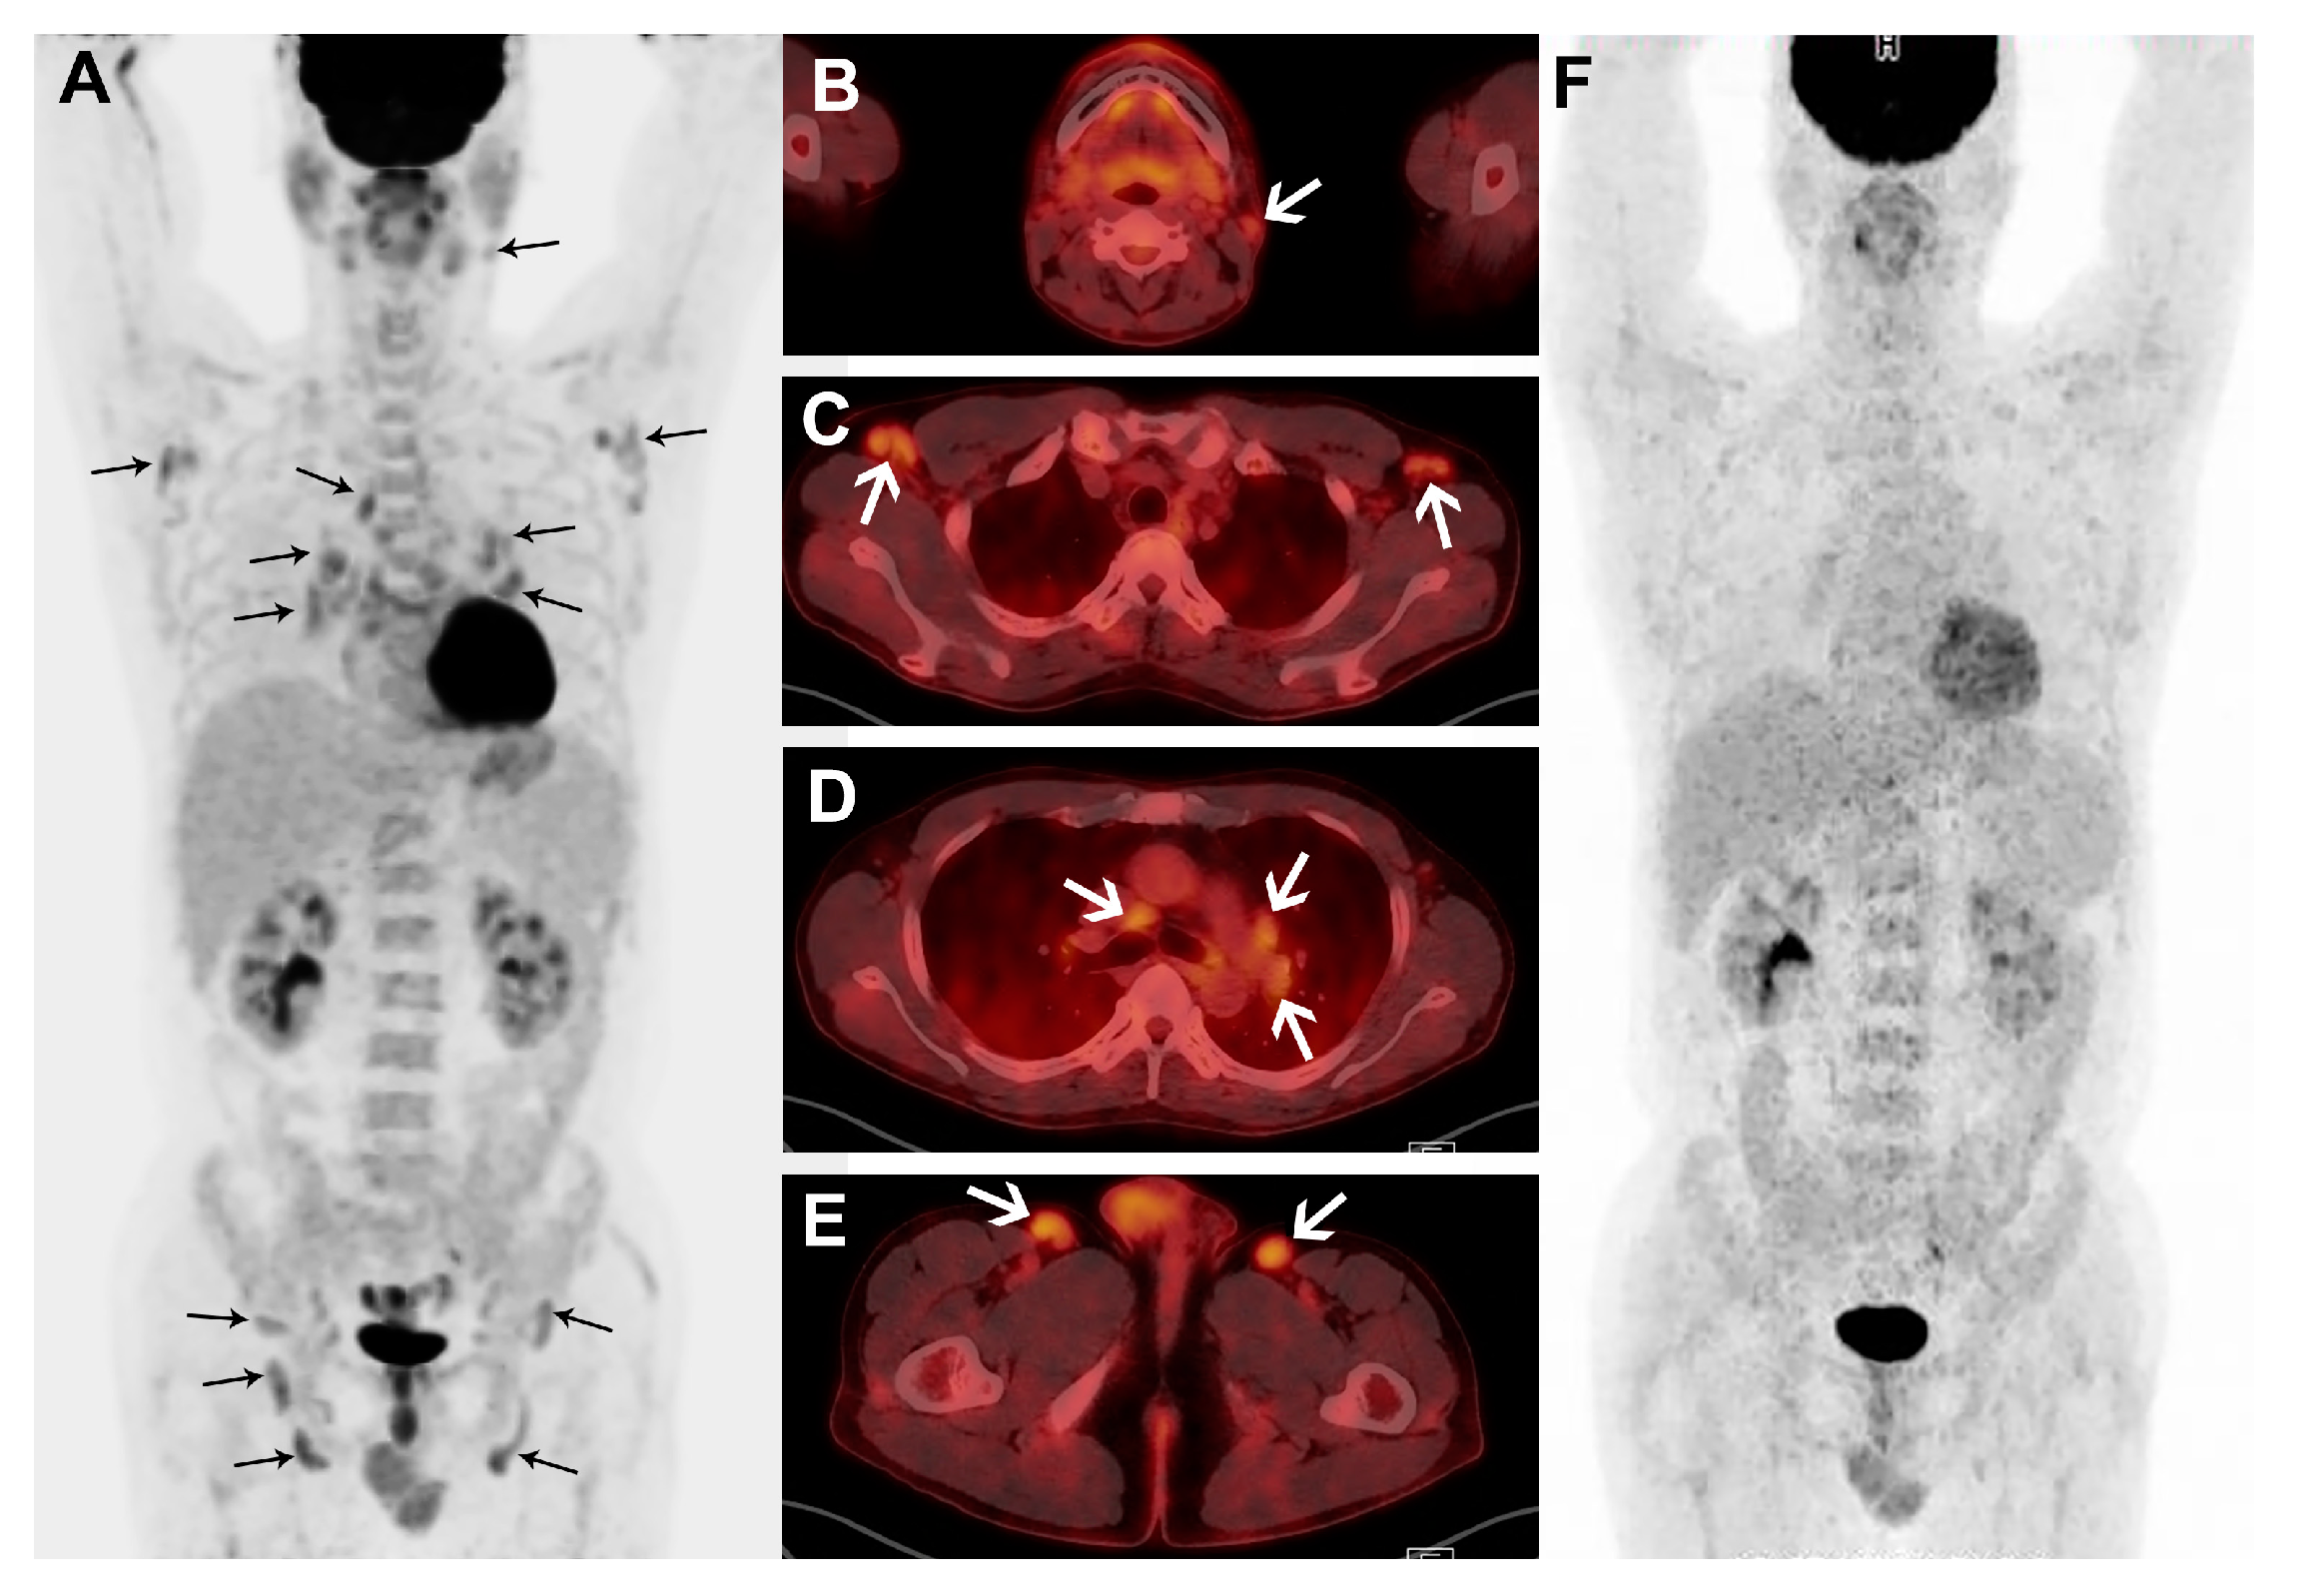

3.2. Visual Assessment of FDG PET/CT

3.3. Quantitative Assessment of FDG PET/CT